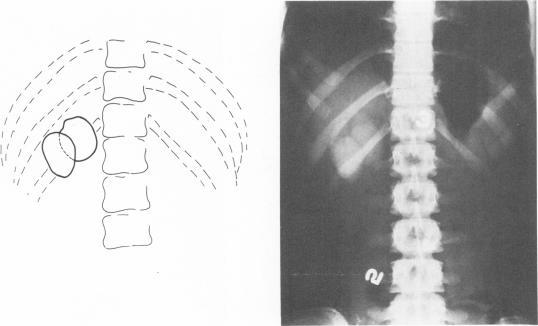

Glenn F, McSherry C K

Ann Surg. 1973 Jun;177(6):705-13. doi: 10.1097/00000658-197306000-00009.